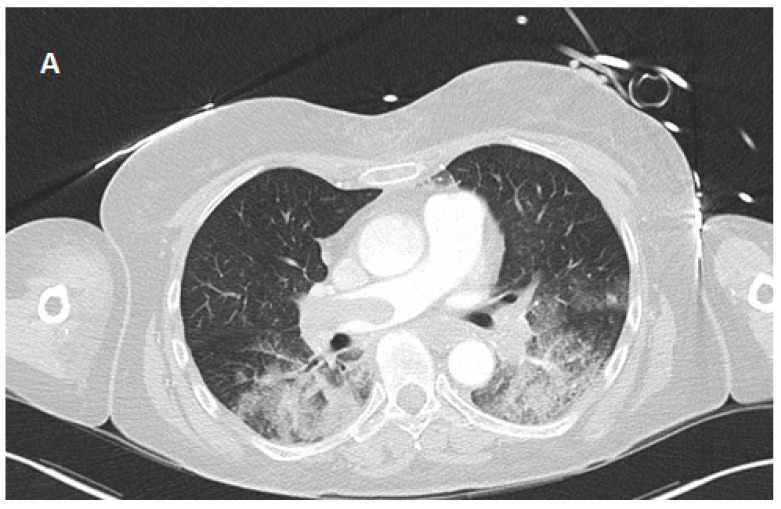

Background and Clinical Significance: Fulminant pulmonary embolism (PE) leading to an out-of-hospital cardiac arrest (OHCA) is associated with a high mortality rate and cardiopulmonary resuscitation (CPR) frequently failing to achieve return of spontaneous circulation (ROSC). Extracorporeal CPR (eCPR) has emerged as a potential life-saving intervention. Case Presentation: A 66-year-old woman suffered an OHCA due to massive PE, presenting with pulseless electrical activity (PEA). After 90 min of pre- and in-hospital CPR without sustained ROSC, venoarterial extracorporeal membrane oxygenation (va-ECMO) was initiated as eCPR upon arrival at the hospital. Even after implantation of the va-ECMO, there was initially a pronounced acidosis (pH 6.9) with a high elevated lactate level (>30 mmol/L); these factors, together with the prolonged low-flow period, indicated a poor prognosis. Further diagnostic tests revealed intracranial hemorrhage (subdural hematoma), and systemic lysis was not possible. With persistent right heart failure, surgical thrombectomy was performed during hospitalization. Intensive multidisciplinary management finally led to successful therapy and weaning from mechanical ventilation, as well as to complete neurological recovery (CPC-Score 1-2). Conclusions: This case illustrates that eCPR can facilitate survival with good favorable neurological outcomes despite initially poor prognostic predictors. It underscores the importance of refining patient selection criteria and optimizing management strategies for eCPR in refractory cardiac arrest secondary to PE.